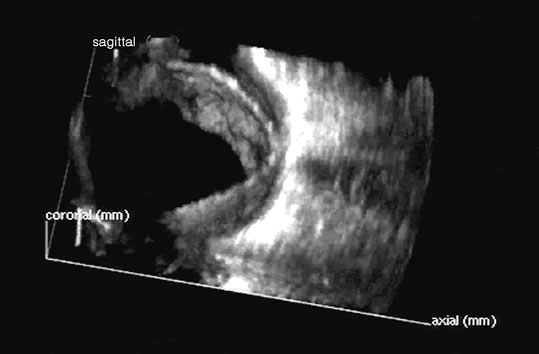

in Medicine. New York, Plenum Press. 1978 14. Coleman DJ, Jack RL: B-scan ultrasonography in diagnosis and management of retinal detachments. Arch Ophthalmol 90:29, 1973 15. Bronson NR, Fisher YL, Pickering NC: Ophthalmic Contact B-Scan Ultrasonography for the Clinician. Westport, CT, International Publication, 1976 16. Downey DB, Nicolle DA, Levin MF, Fenster A: Three-dimensional ultrasound imaging of the eye. Eye 10:75, 1996 17. Coleman DJ, Daly SW, Atencio A, et al: Ultrasonic evaluation of the vitreous and retina. Semin Ophthalmol 13:210, 1998. 18. Wu G, Silverman RH, Coleman DJ, et al: In vivo thickness of human detached retina by ultrasonic signal processing. Graefes Arch Clin Exp Ophthalmol 227:21, 1989 19. Coleman DJ, Rondeau MJ: Diagnostic imaging of ocular and orbital trauma. In Shingleton BJ, Hersh PS, Kenyon KR (eds): Eye Trauma, pp 25–40. St. Louis, Mosby-Year Book, 1991 20. Clemens S, Kroll P, Rochels R: Ultrasonic findings after treatment of retinal detachment by intravitreal

of the posterior segment. Retina 18:251, 1998 42. Atta HR: New applications in ultrasound technology. Br J Ophthalmol 83:1246, 1999 43. Basset O, Gimenez G, Mestas JL, et al: Volume measurement by ultrasonic traverse or sagittal cross-sectional

scanning. Ultrasound Med Biol 17:291, 1991 44. Kidd MN, Lyness RW, Patterson CC, et al: Prognostic factors in malignant melanoma of the choroid: A retrospective